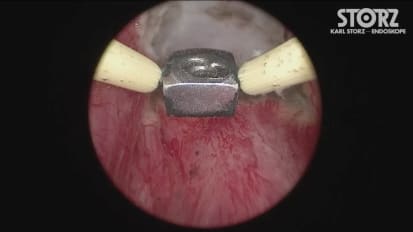

Minimally Invasive PCNL: MIP

Minimally Invasive PCNL Technique and Demo

Minimally Invasive PCNL (MIP) is more than a mini-perc. This system takes advantage of single-step dilation and the vacuum effect to remove stones with minimal trauma and faster procedure times. Send your patients home with just a bandage.

Mini PCNL Instrumentation and Demo

Dr. Seth Bechis of UC San Diego introduces the reusable instrument set needed to perform minimally invasive PCNL on an outpatient basis and demonstrates procedural steps, including the vacuum effect.